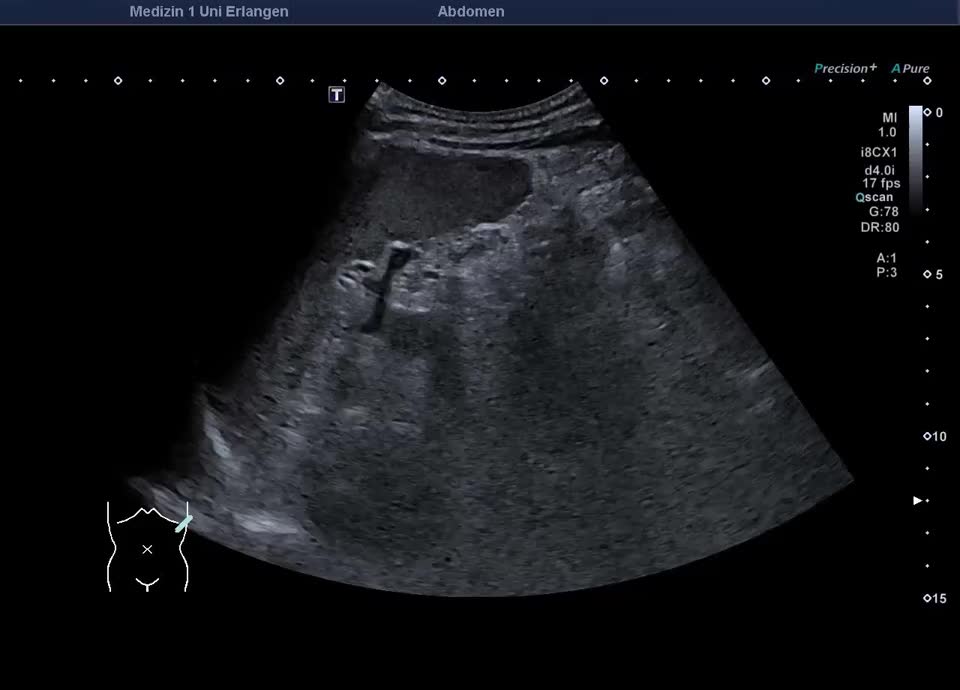

47-year-old patient presents to the emergency department with flank pain. Ultrasound shows a large, inhomogeneous, sharply defined mass in the left adrenal gland. A blood sample (including metanephrines) and a puncture (endosonographic access) are initiated for further clarification. Histologically adrenal cancer